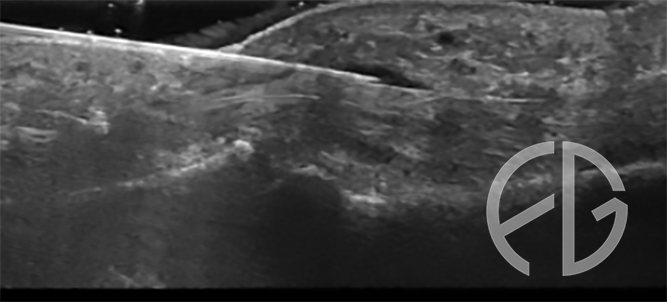

La tecnologia ci è venuta incontro e gli ecografi di nuova generazione ci permettono di visualizzare con ESTREMA PRECISIONE le strutture anatomiche coinvolte nel dito a scatto. Non solo, l’ecografia è uno degli strumenti diagnostici più affidabili nella diagnostica differenziale sulle cause del dito a scatto (primitive, secondarie etc), e le nuove sonde ad altissima frequenza (24Mhz) permettono una visualizzazione perfetta di queste strutture.

Un ecografista esperto in interventistica sarà in grado di risolvervi il dito a scatto con una procedura RAPIDA, EFFICACE, SICURA E SENZA CICATRICI! il rilascio della puleggia si esegue per via percutanea con un forellino di appena 0,5 mm!